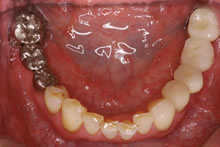

【2】3ヶ月後、最終のセラミックの人工歯が入った状態